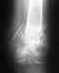

Подскажите пожалуйста месяц назад травмировал кисть, пришел сделал снимок

врач сказал что был перелом но срослось хорошо, я не увидел перелома подскажите есть ли место на естом снимке перелому и в каком месте